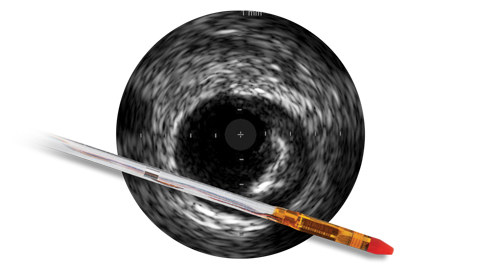

Angiography provides information on luminal characteristics of vessels, but does not provide a clear picture of the vessel and disease.

However, with IVUS guidance you can see more clearly and improve patient outcomes with informed pre-stent planning and post-stent optimization.1